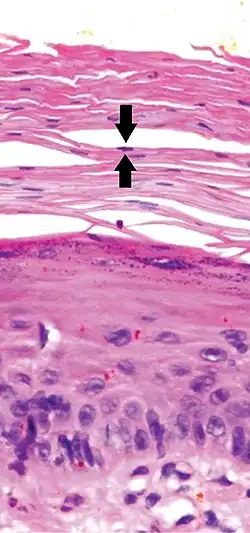

Early actinic keratosis with parakeratosis, with black arrows indicating one of multiple retained nuclei in the stratum corneum

Parakeratosis is a mode of keratinization characterized by the retention of nuclei in the stratum corneum.[1] In mucous membranes, parakeratosis is normal.[2] In the skin, this process leads to the abnormal replacement of annular squames with nucleated cells. Parakeratosis is associated with the thinning or loss of the granular layer and is usually seen in diseases of increased cell turnover, whether inflammatory or neoplastic. Parakeratosis is seen in the plaques of psoriasis and in dandruff.